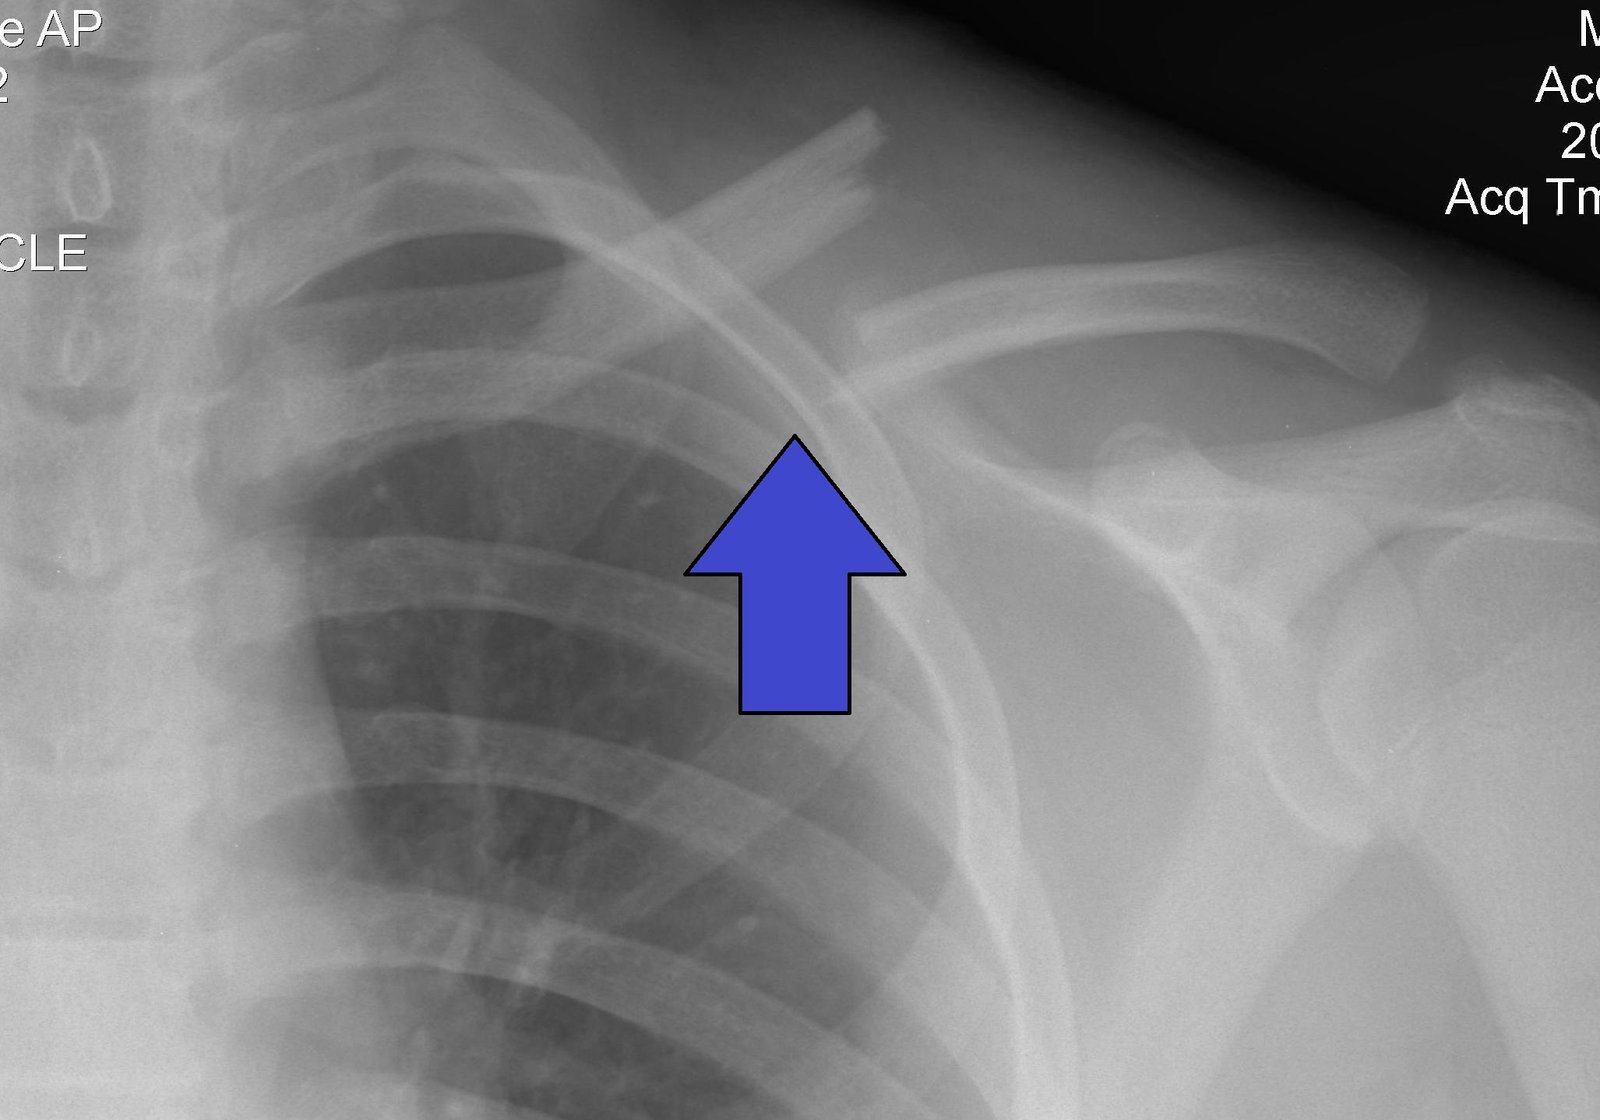

Fracture of clavicle | CHAPTER 5 | Orthopedic Nursing

Sites of clavicle fractures:

1. At the junction of middle and outer third of clavicle (85%)

2. Medial end of the clavicle (5%).

3. Lateral end of clavicle (About 10%).